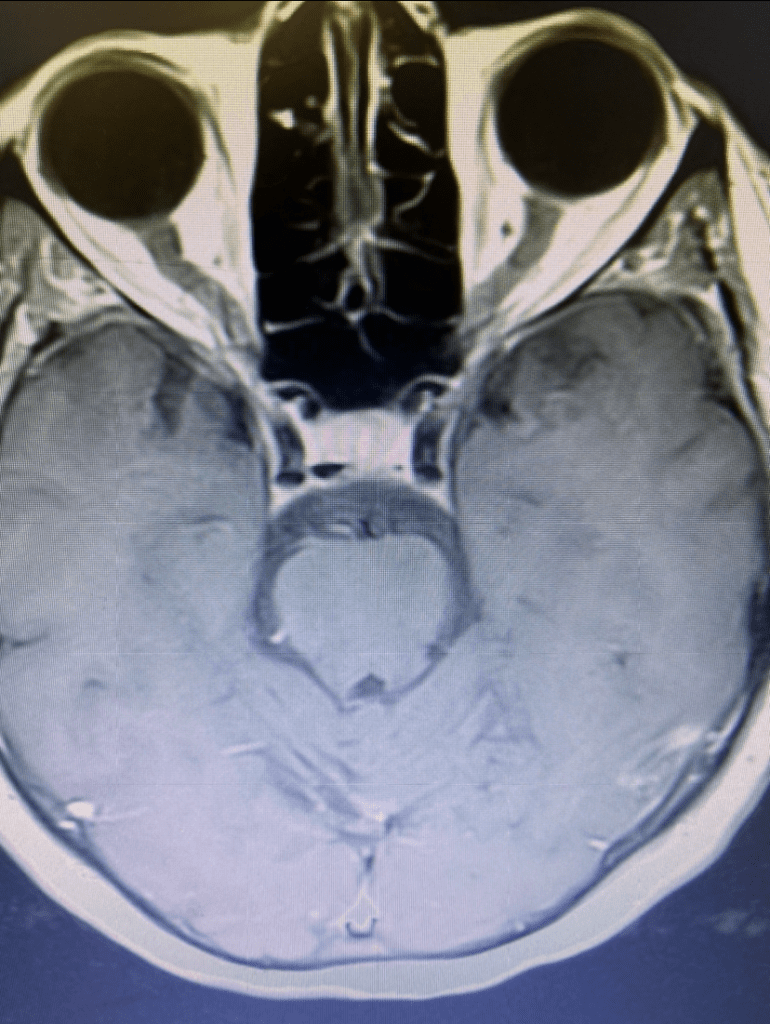

She returned for a follow up visit 19 years after the Gamma Knife treatment just to check up on things. She felt well and was neurologically intact. MRI and CTA of the brain were performed, which demonstrated complete obliteration of the AVM.

Figure 2A. Axial MRI with contrast.